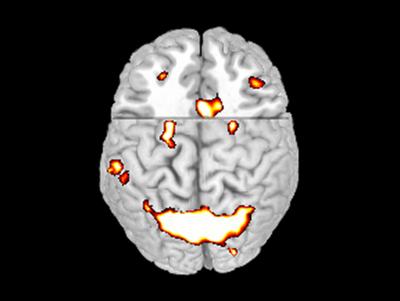

Brain Scan of Active Areas

image: A brain scan illustrates areas that became active when the subject was presented with a stimulus. In this study, those same areas also became active when the subject was cued to the task, indicating that the same areas of the brain that respond to stimulus also contribute to preparation. view more

Credit: Eric Schumacher/Georgia Tech